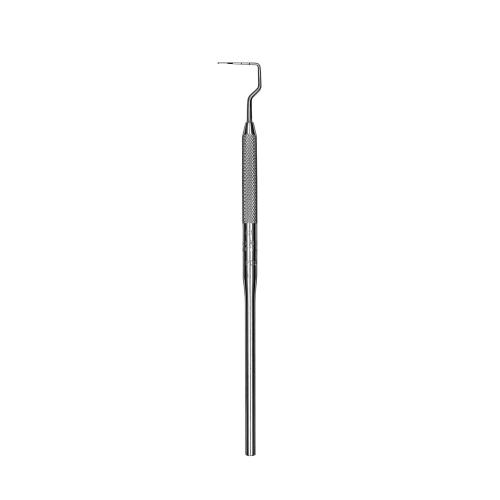

Parodontometro Novatech #NT11 Qulix 3-6-8-11

Parodontometro Novatech #NT11 Qulix 3-6-8-11

Parodontometro Novatech #NT11 Qulix 3-6-8-11

Parodontometro Novatech #NT11 Qulix 3-6-8-11

Cod

PCPNT11

PCPNT11

Novatech, color-coded probe.

46,80 €

Unique right angle design for improved adaptability in posterior regions. QulixŖ probes are color-coated with accurate, smoothly finished black markings which will not chip, flake or fade.